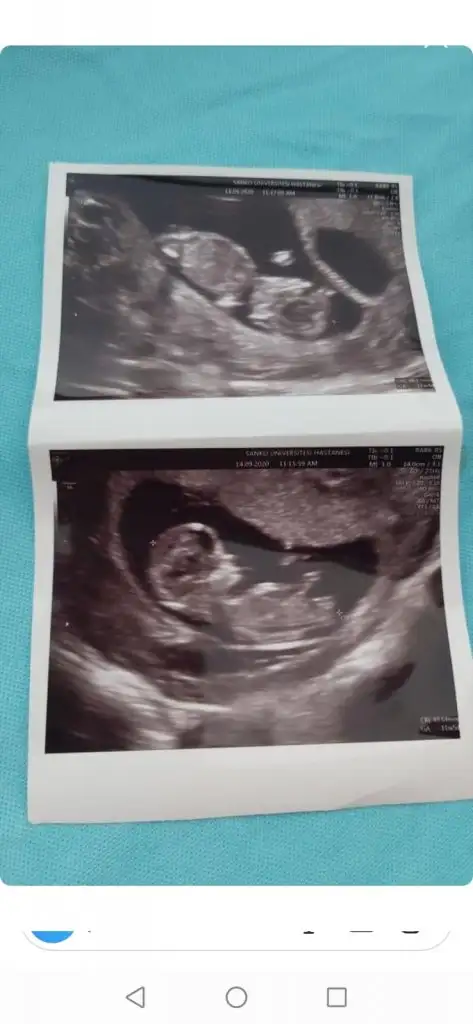

Çok net değil üsteki sanki kız altaki erkek gibi diyecem emin olamadım başka USG varsa paylaşınMerhaba arkadaşlarımın ikizlerini de yorumlar mısınız 12. HaftadalarEki Görüntüle 2698252

Sağ usteki erkek gibi tek tek çeksen belki net olur USG diğeride kız sanki

Çektim canımSağ usteki erkek gibi tek tek çeksen belki net olur USG diğeride kız sanki